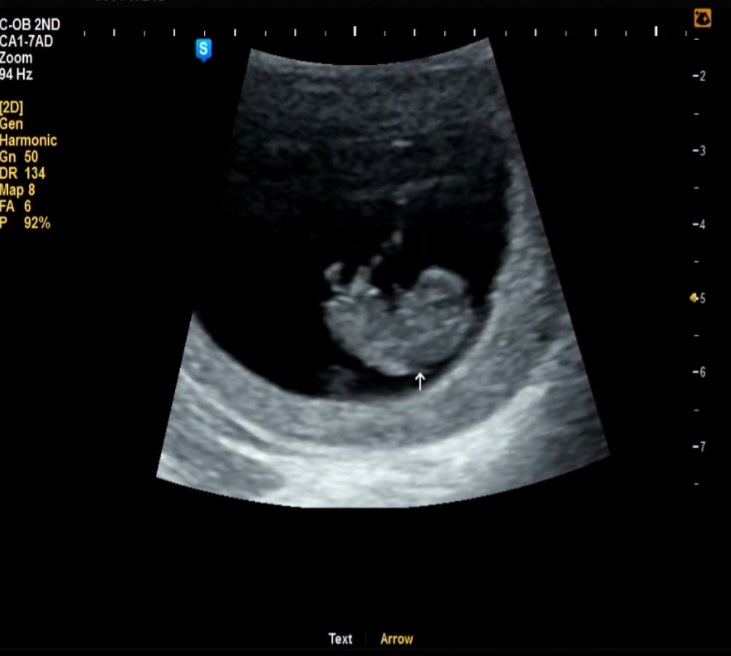

8주6일차 젤리곰실패..!

글 처음 써보네요 병원에서 3주뒤에 오라고 해서 좀 걱정했는데 잘 크고 있다고 하니 마음이 놓였어요 8주6일차여서 8월 30일 출산예정이에요 팔다리가 생겼더라구요! 팔다리를 움직이는데 너무 귀여웠어요ㅋㅋㅋ 남편이 젤리곰이 아니고 매미유충같다고...ㅋㅋ 공감되었지만 어쨋든 2.34센치라고 하던데 너무 큰건가 싶기도 하고요! 그래도 기쁘네요ㅎㅎ 검단 모임 단톡방이 있다면 알려주심 감사하겠습니다!

매미유충에서 빵터졌어요 ㅋㅋ 저희애기도 8주차때 옆모습만찍어서 젤리곰 실패엿는데 딱 저모습이였거든요 ㅎㅎㅎ

ㅋㅋㅋ옆모습만 보여준데다가 고개를 숙이고 있어서 더 매미처럼 보였던거같아요.. 아쉬어용